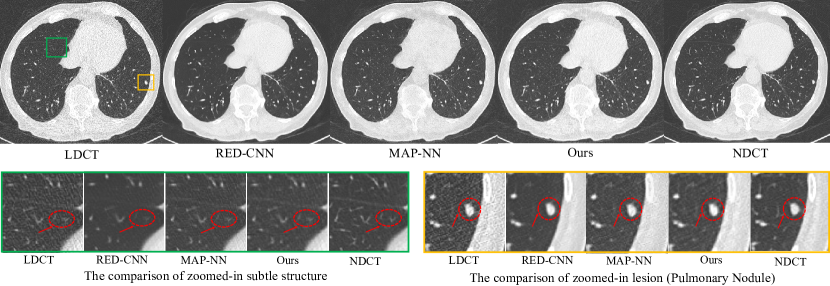

The analysis of visual results for zoomed-in subtle structure and lesion. Abdomen: As shown in Figure 10, we can make some important observations. First, the green box shows the comparison of zoomed-in subtle structure, we can find these structures (within red circles) nearly disappear for RED-CNN, due to the easily observed over-smoothness. Similarly, MAP-NN suffers from the same problem and also has a slight over-smoothness. Instead, our proposed model greatly preserves the subtle structure and generates the texture closest to NDCT. Both RED-CNN and MAP-NN only leverage the local information by the CNN, so it is difficult to balance the local detail and noise removal with limited information. Our proposed model adopts the framework of multi-information fusion such that extra information can be used as a supplement to produce the optimal results regardless of structure and texture. Second, as illustrate in the red circle of yellow box in Figure 10, our proposed model has the most obvious observation for the lesion (diagnosed as Metastasis-Esophageal), especially for the level of the grayscale. However, the lesion in RED-CNN and MAP-NN becomes very fuzzy. The superiority of lesion region further proves the effect of multi-information fusion framework. Chest: As shown in the yellow box of Figure 11, we can find that all models achieve the preservation of lesion (within the red circle). However, MAP-NN has more easily observed noise points compared with RED-CNN and our proposed model. RED-CNN losses the subtle structure basically as shown in red circle of green box. In summary, our proposed model has the most impressive visual performance, which naturally obtains the best performance of double-blind study as reported in Figure 8 and 9.